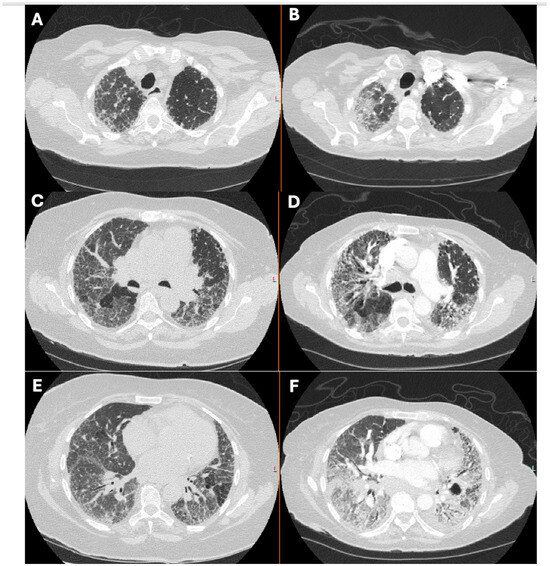

1.1. The Diagnosis and Evaluation of Patients with ILD in the ICU

- Charokopos, A.; Moua, T.; Ryu, J.H.; Smischney, N.J. Acute exacerbation of interstitial lung disease in the intensive care unit. World J. Crit. Care Med. 2022, 11, 22–32. [Google Scholar] [CrossRef]

- Suzuki, A.; Kondoh, Y.; Brown, K.K.; Johkoh, T.; Kataoka, K.; Fukuoka, J.; Kimura, T.; Matsuda, T.; Yokoyama, T.; Fukihara, J.; et al. Acute exacerbations of fibrotic interstitial lung diseases. Respirology 2020, 25, 525–534. [Google Scholar] [CrossRef]

- Alhamad, E.H.; Cal, J.G.; Alrajhi, N.N.; AlBoukai, A.A. Acute exacerbation in interstitial lung disease. Ann. Thorac. Med. 2021, 16, 178–187. [Google Scholar] [CrossRef]

- Martin, M.J.; Moua, T. Mechanical Ventilation and Predictors of In-Hospital Mortality in Fibrotic Interstitial Lung Disease with Acute Respiratory Failure: A Cohort Analysis Through the Paradigm of Acute Respiratory Distress Syndrome. Crit. Care Med. 2020, 48, 993–1000. [Google Scholar] [CrossRef]

- Matsunashi, A.; Nagata, K.; Morimoto, T.; Tomii, K. Mechanical ventilation for acute exacerbation of fibrosing interstitial lung diseases. Respir. Investig. 2023, 61, 306–313. [Google Scholar] [CrossRef] [PubMed]

- Marchioni, A.; Tonelli, R.; Rossi, G.; Spagnolo, P.; Luppi, F.; Cerri, S.; Cocconcelli, E.; Pellegrino, M.R.; Fantini, R.; Tabbì, L.; et al. Ventilatory support and mechanical properties of the fibrotic lung acting as a “squishy ball”. Ann. Intensive Care 2020, 10, 13. [Google Scholar] [CrossRef] [PubMed]